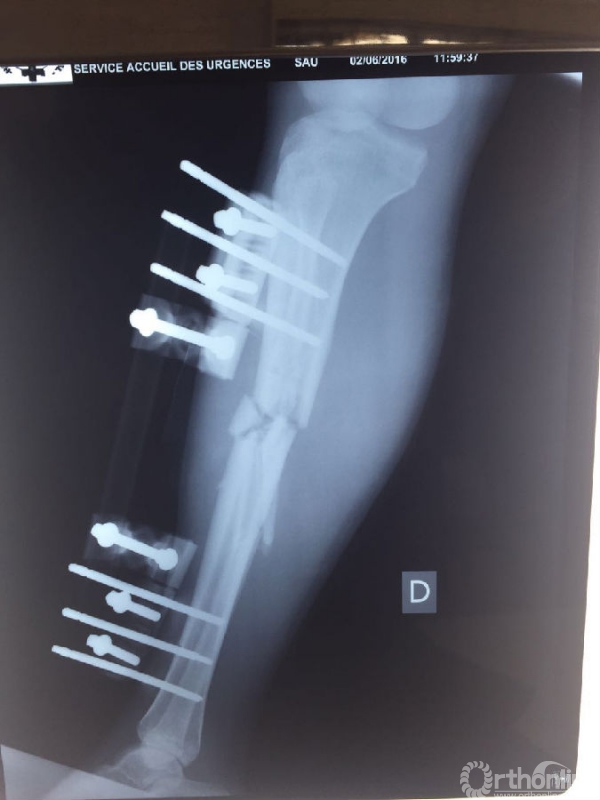

战士李涛,因31日的爆炸袭击导致左大腿及右小腿严重损伤。塞方初期已行右小腿开放性骨折清创外固定架固定及左大腿清创转移皮瓣修复术。杨润功教授亲自给伤员查体换药,仔细观察伤口渗出及皮瓣愈合情况,重新调整了外固定架,叮嘱塞方医护人员加强换药观察,并向伤员及陪护人员详细交代了后期功能康复细节要点。现李涛生命体征平稳,伤口渗出已明显减少。

李涛右小腿X线片